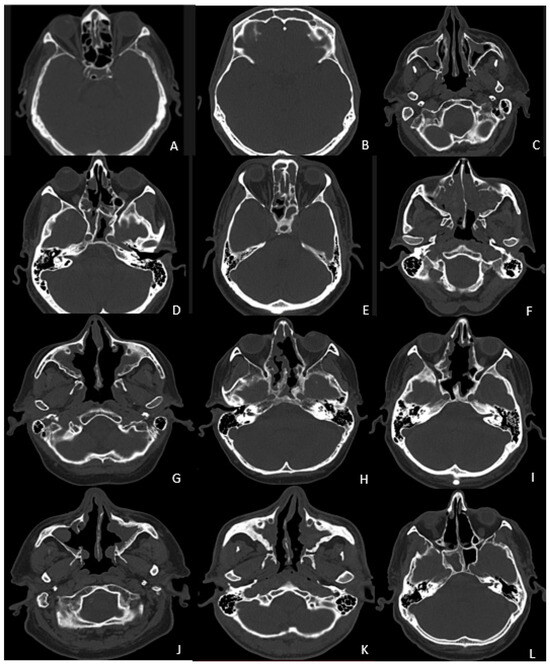

| Scoring System | Evaluated Sites | Grading Description | Total Score |

|---|---|---|---|

| Global Osteitis Scoring Scale | 10 sinuses (right and left frontal, anterior ethmoid, posterior ethmoid, maxillary, and sphenoid) | Grade 1: <50% sinus walls involvement and thickening < 3 mm wide | Composite score range 0–50 |

| Grade 2: <50% sinus walls involvement and thickening 3–5 mm wide | |||

| Grade 3: <50% of sinus walls involvement and thickening > 5 mm wide or >50% sinus walls involved and thickening < 3 mm wide | |||

| Grade 4: >50% of sinus walls involvement and thickening 3–5 mm wide | |||

| Grade 5: >50% of sinus walls involvement and thickening > 5 mm wide |